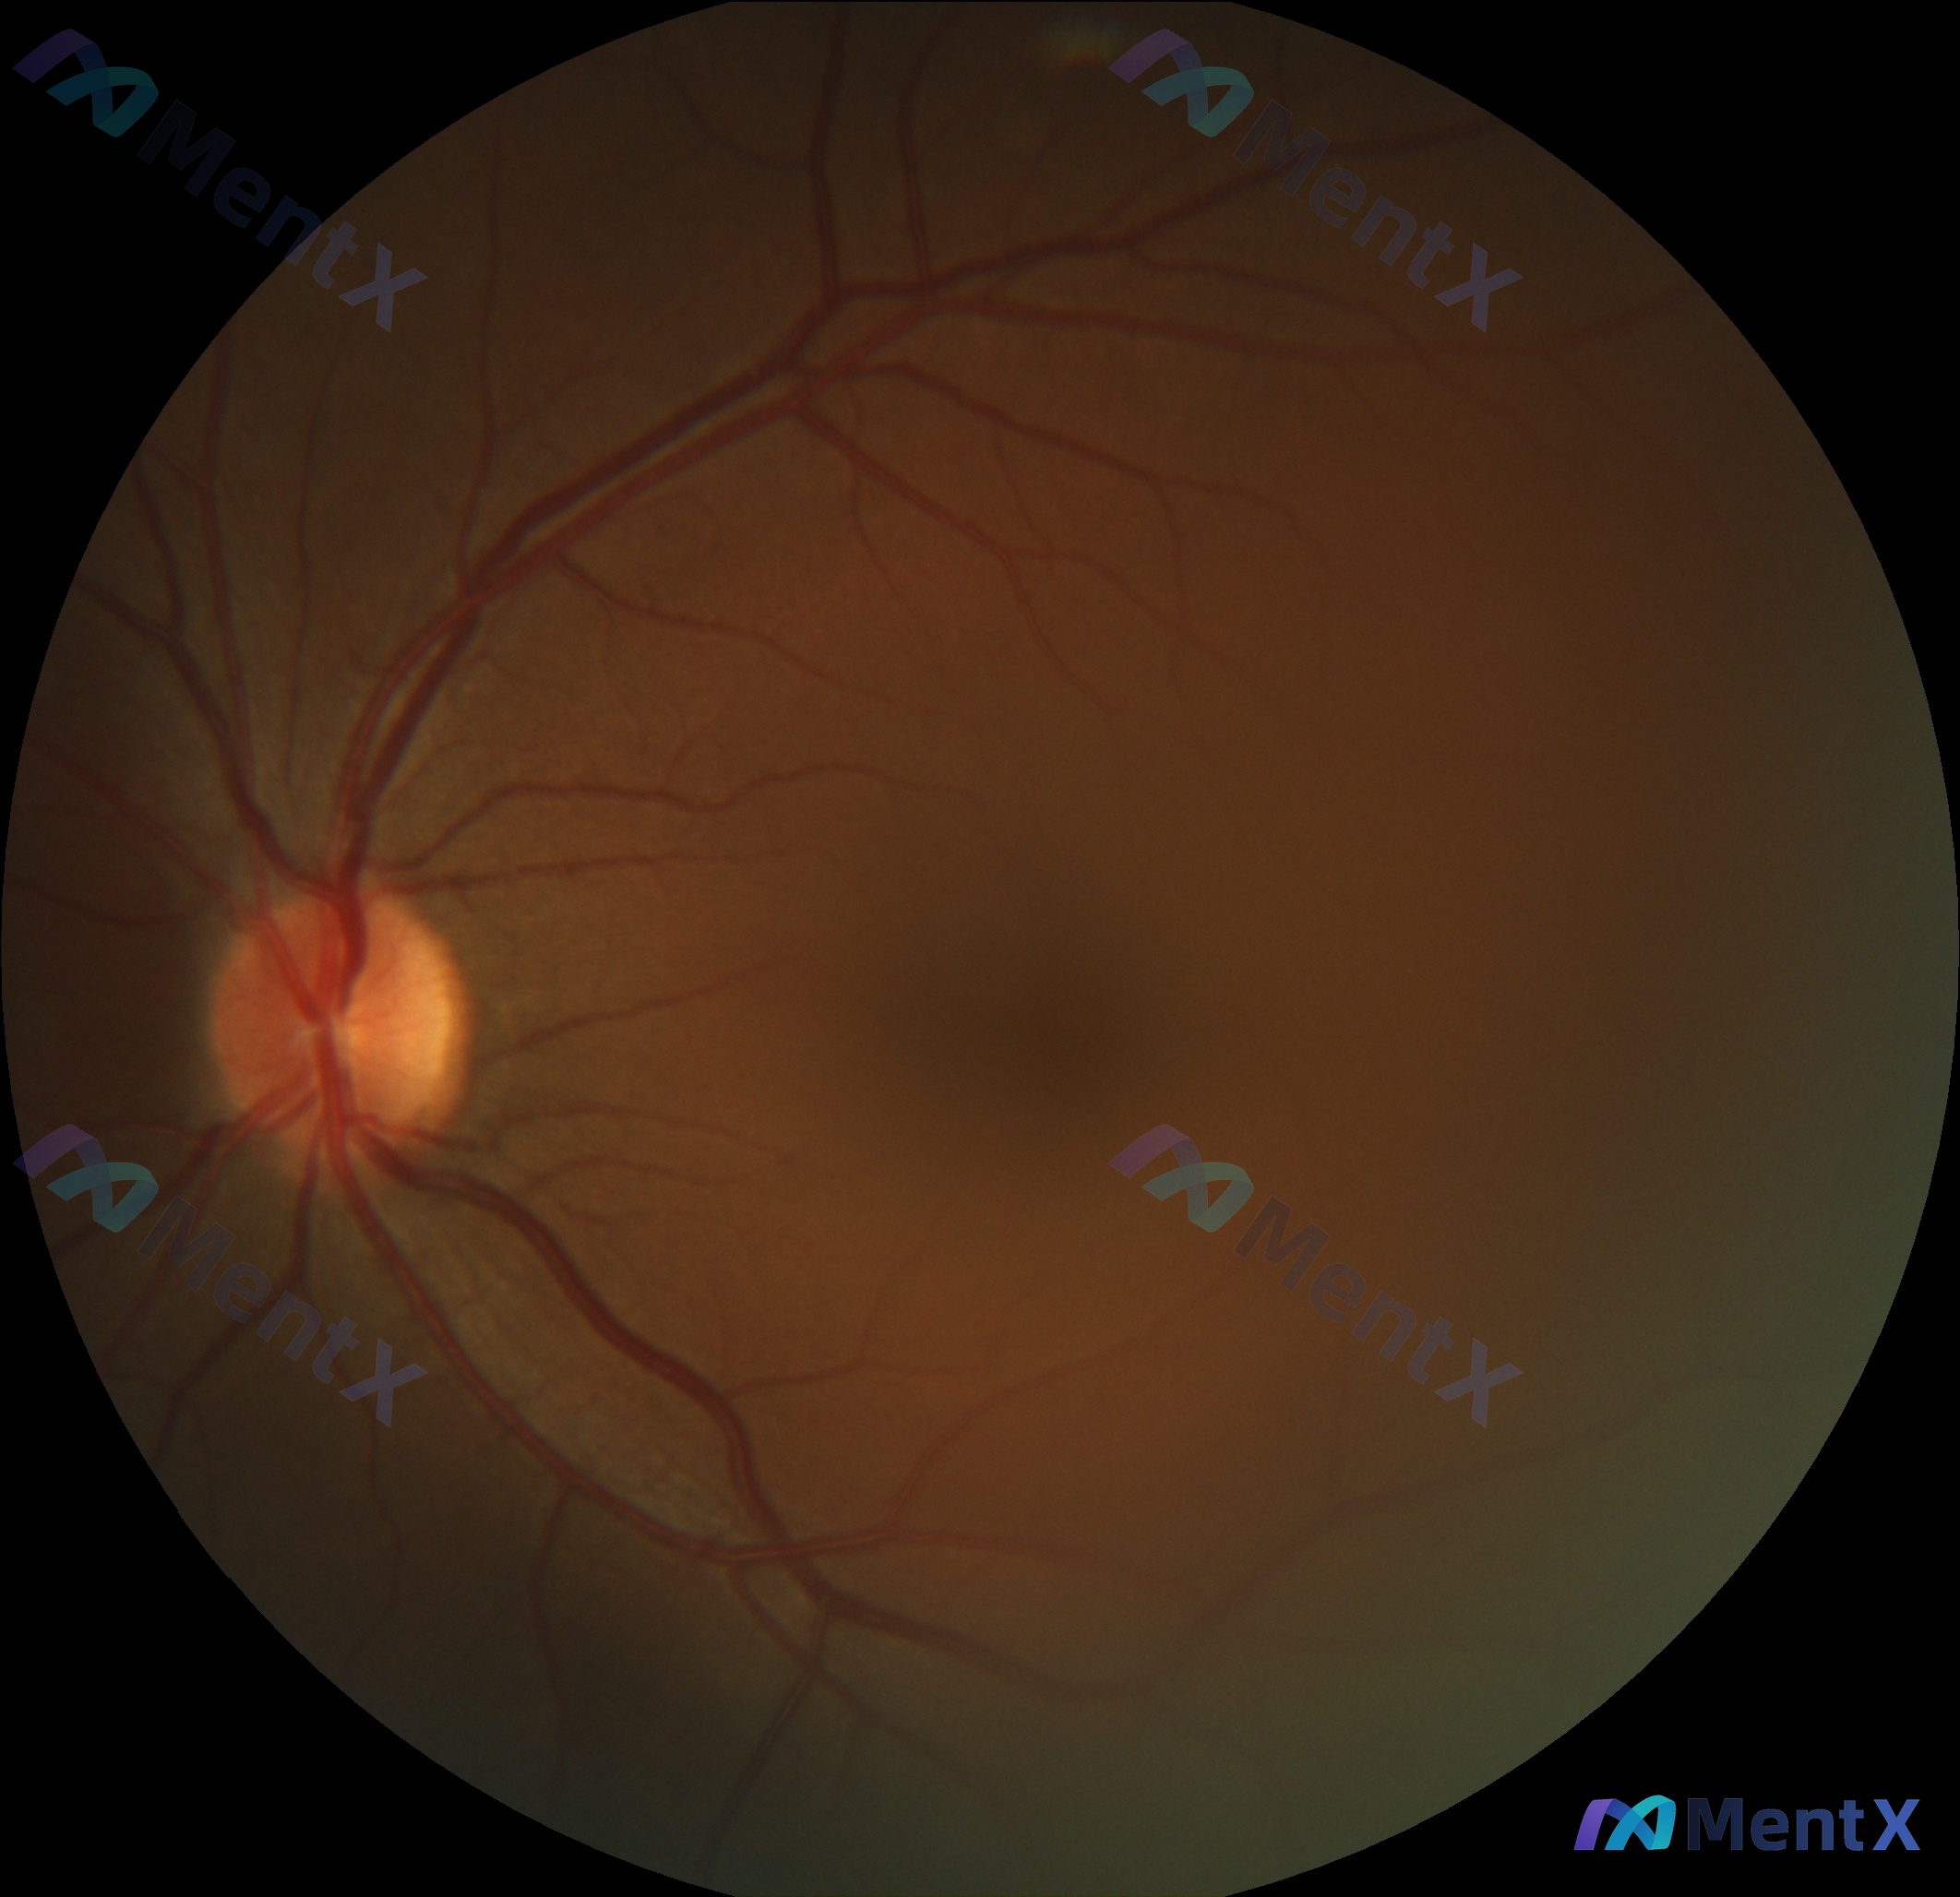

这张眼底视网膜图像,大家觉得有没有异常?

整理到一张眼底视网膜图像的分析资料,先不说结论,仅看描述的影像特征,大家第一眼会怎么判断?

影像表现大概是:

- 视盘轮廓清晰,边界锐利,颜色淡红,杯盘比在生理范围内,血管走行自然

- 黄斑中心凹反射存在,无水肿、裂孔或色素紊乱

- 视网膜动静脉比例约2:3,走形规律,无微血管瘤、出血或渗出

- 玻璃体清晰,成像范围内视网膜平伏

这份资料的核心问题就是:这张图像到底有没有异常?